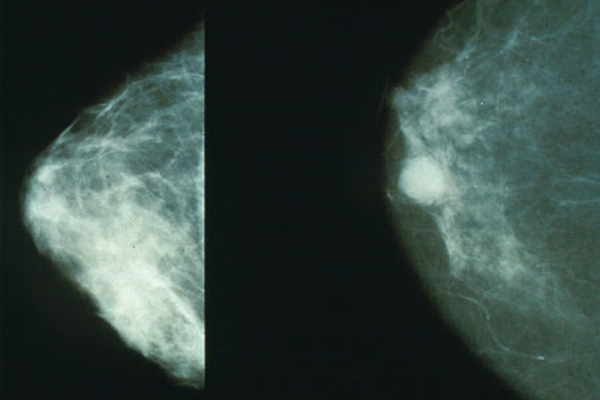

2- قد تسبب الصورة الشعاعية للثدي انتشار المرض إذا كان موجوداً

الحقيقة: لا تسبب الصورة الشعاعية للثدي انتشار المرض. فكما أن الأشعة لا تشكل خطراً كذلك الضغط على الثدي لا يؤدي إلى انتشار الورم. في الواقع، تعتبر الصورة الشعاعية للثدي وسيلة الكشف المبكر الفضلى للمرأة بعد سن الأربعين.